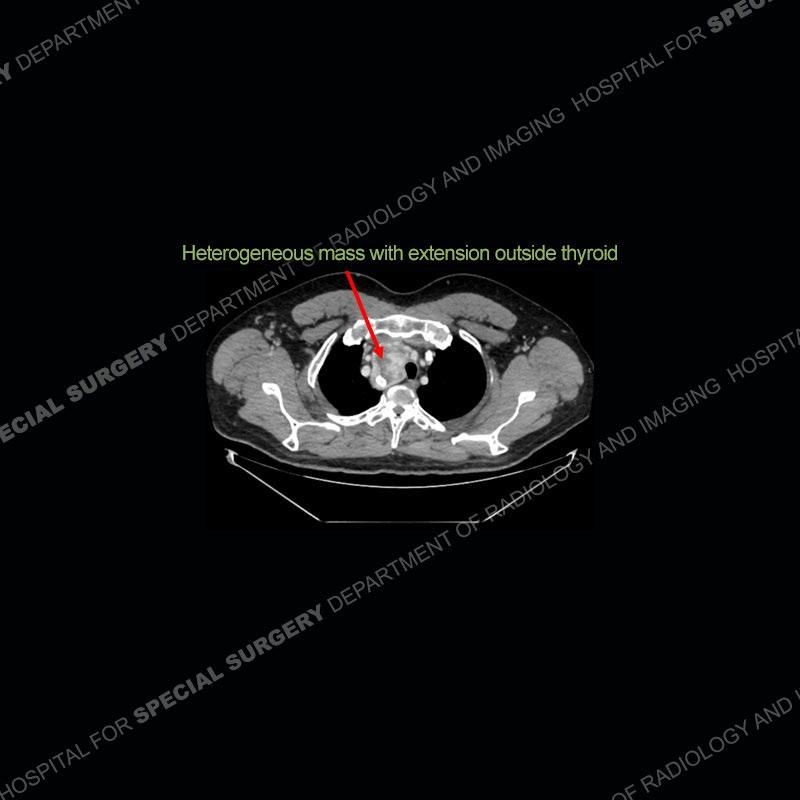

The chest radiographs demonstrate a leftward deviation of the trachea. CT images demonstrate a large, somewhat heterogeneous mass of the thyroid that extends outside the confines of the thyroid tissue. There is a subtle, enhancing soft tissue mass of the proximal right humerus. Slightly prominent mediastinal lymph nodes are present with additionally, multiple supraclavicular lymph nodes.

Over the years we have shown a couple of these cases which may be considered more so an “eye test” then anything else. In clinical practice, these are often very difficult cases as the initial finding of the tracheal deviation may be easily overlooked. Screening radiographs are clearly most often used to assess cardiopulmonary function before induction of anesthesia but at times other findings of great and unfortunately grave consequence can be found. The evaluation of the incidental thyroid mass on CT and MRI is an ever changing situation. Parameters such as age of patient, extension outside of the thyroid, enhancing nodules, and local invasion of lymph nodes are evaluated to see if a lesion needs to be further evaluated.